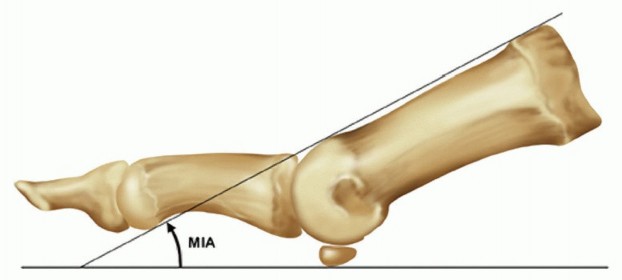

4. Positioning and Alignment (The Critical Step)

Achieving the correct three-dimensional alignment is the most crucial step in preventing postoperative complications such as interphalangeal joint arthritis, hallux hammering, or transfer metatarsalgia.

* Valgus: The hallux should be positioned in 10 to 15 degrees of valgus, ensuring it rests parallel to the second toe without impinging on it.

* Dorsiflexion: The hallux must be positioned in 10 to 15 degrees of dorsiflexion relative to the floor (simulated weight-bearing), which equates to approximately 20 to 25 degrees of dorsiflexion relative to the longitudinal axis of the first metatarsal.

* Rotation: The toe must be in neutral rotation. The toenail should face directly dorsal.

Pitfall: Excessive dorsiflexion leads to shoe-wear irritation and a "cocked-up" toe. Inadequate dorsiflexion (a toe that is too straight or plantarflexed) causes severe vaulting during gait, excessive pressure on the interphalangeal joint leading to rapid arthritis, and an inability to wear shoes with any heel elevation.